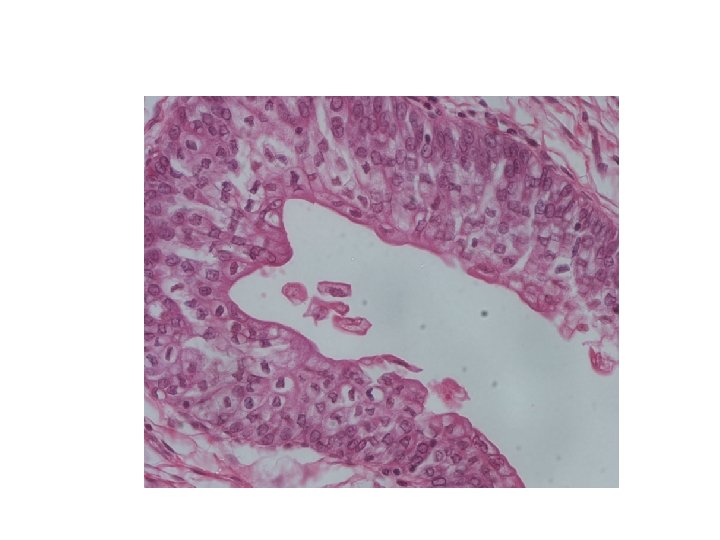

9. Question Name the type of epithelium in the following slide.

Answer Transitional Epithelium of Ureter Question Board